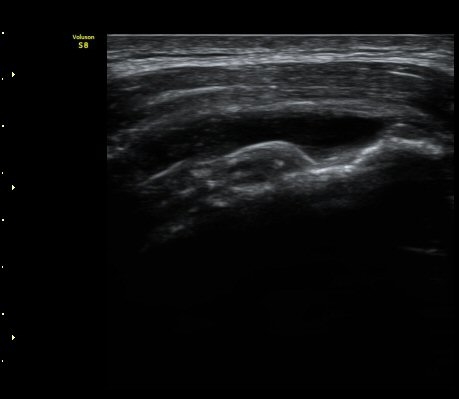

±Ø»ó°Ç Á¾´Ü¸é°Ë»ç¿¡¼­ ±Ø»ó°ÇÀÇ ÀüÃþÆÄ¿­°ú ±Ø»ó°ÇÀ» ¿¬°áÇÑ ºÀÇջ簡 Á÷¼± À¸·Î °üÂûµÈ´Ù(»çÁø 3, 4)